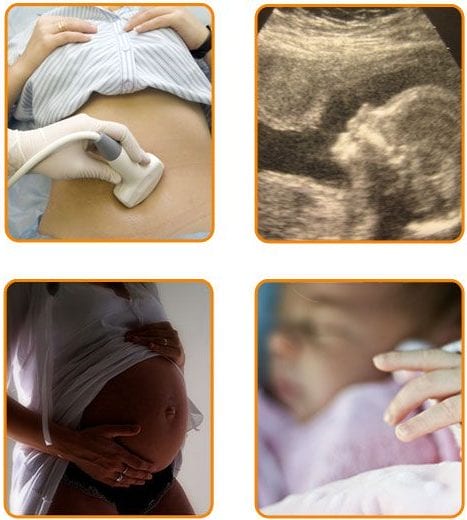

Sarcina, ultimul stadiu în FIV reușită

La 14 zile de la recoltarea ovulelor se efectuează testul de sarcină. În cazul în care este pozitiv urmează o ecografie vaginală care certifică existența sacului embrionar și mai târziu a bătăilor cordului fetal.

La centrul FIV MITOSIS personalul specializat asigură urmărirea atentă și competentă a gravidei pe toată durata sarcinii.